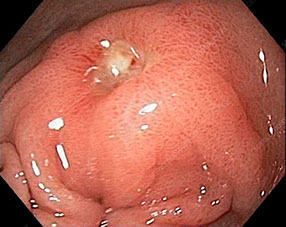

Polipectomía Avanzada: Resección Endoscópica de la Mucosa (REM)

La resección endoscópica de la mucosa, o REM, utiliza un endoscopio especialmente diseñado para retirar tejido o pólipos sospechosos del esófago, estómago o duodeno. Luego se utiliza la succión para levantar el bulto y separarlo del tejido que lo rodea. Con ello se consigue la eliminación de lesiones sospechosas de albergar cáncer desde la raíz.